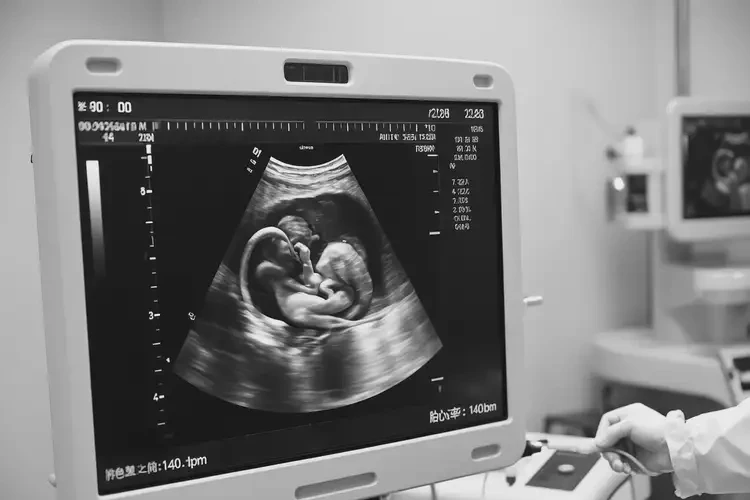

孕20周1天胎心80多還能保住嗎(圖1)

• 超聲檢查:觀察胎兒的生長(zhǎng)發(fā)育情況、胎盤和臍帶的狀態(tài)等。

孕20周1天胎心80多還能保住嗎(圖2)